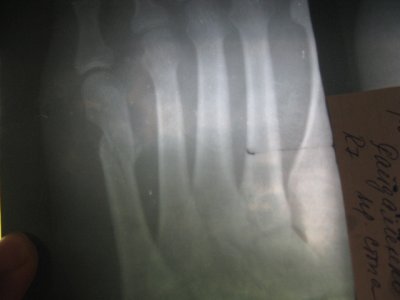

4 апреля 2012г. вечером на репетиции упала на правую ногу. в этот же день через час обратилась в травм.пункт, сделали снимок, обнаружили:Закрытый косой перелом 5 плюсневой кости со смещением, наложили гипсовую повязку от кончика большого пальца до середины икры с заходом по бокам на ступню (сверху ступни и нижней части икры впереди гипса нет).Сказали через неделю приехать для контрольного снимка.

12 апреля 2012г. сделала повторный снимок,после которого мне сказали нужно делать операцию,вставлять либо пластину,либо спицы!Сказали без операции будет заживать пол года,а после операции всего месяц, полтора! Первого снимка нет,на руки не отдали,а вот повторный постараюсь отправить сюда!

Вот на этом сайте нашла очень похожий снимок и написано что можно обойтись без операции! Буду вам очень признательна за помощь и консультацию!

Скажите правда у меня тяжелое состояние ,что без операции ни как? и если можно обойтись без операции,то какие меры нужно принимать,чтобы кость благополучно срасталась? И сколько она будет срастаться без операции? Сколько нужно будет носить гипсовую повязку? Когда можно будет наступать на ногу?